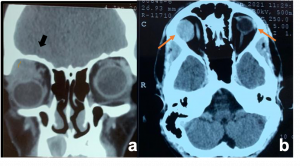

| Preseptal Cellulitis | More common in < 5 years of age group | Lid edema, erythema | CT- shows stranding, swelling, variable enhancement of the preseptal soft tissues anterior to the globe

Sub Periosteal Abscess. Coronal contrast-enhanced CT image of right orbit showing extraconal marginally enhancing fluid collections located superonasally, consistent with subperiosteal abscess. These are present in continuation with opacified right ethmoidal air cells and right maxillary antrum with soft tissue density with hyperdense content. |

| Orbital Cellulitis | More common in > 5 years of age group | Proptosis, chemosis, limitation of EOM, fever | CT- early- eyelid edema and sinusitis

Marked postcontrast enhancement. Inflammation is seen in the medial or superomedial orbit adjacent to the opacified sinus, associated with fat stranding

| Sub periosteal abscess[14] | No age/gender predilection | Collection of subperiosteal fluid causing abaxial proptosis along with other signs of cellutlitis | CT- shows hypodense, convex collection with ring enhancement present along orbital wall

| |